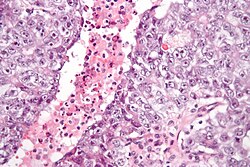

| Choriocarcinoma | clear cytoplasm | cells with abundant clear cytoplasm and eccentric atypical nuclei (cytotrophoblast), very large (multinucleated) cells with abundant eosinophilic cytoplasm and extreme nuclear atypia (syncytiotrophoblast) | beta-hCG +ve | may be preceded by a complete hydatidiform mole | File:Choriocarcinoma -2- very high mag.jpg Choriocarcinoma. (WC/Nephron) |